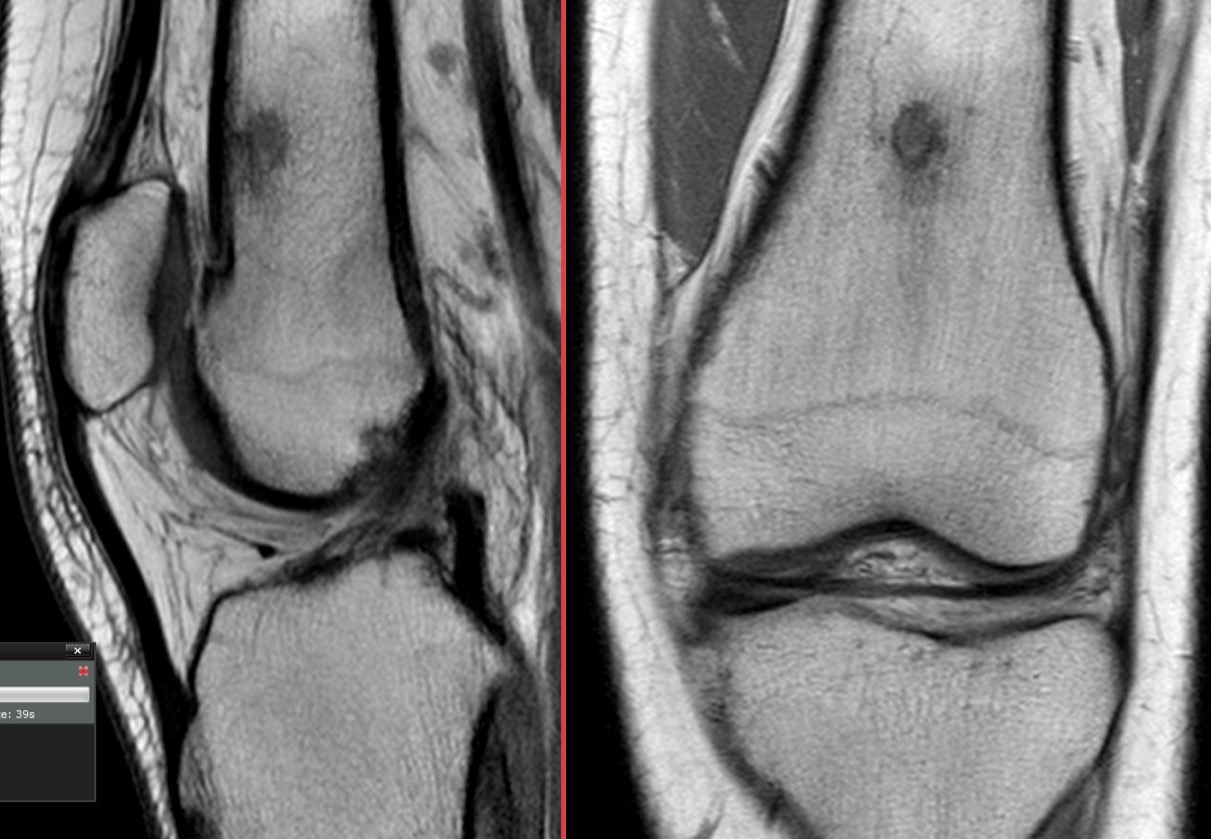

Figure 3 for case osteoid osteoma ( RID4005 )

Figure 3

Figure 4 for case osteoid osteoma ( RID4005 )

Figure 4